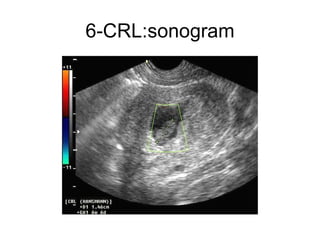

6-CRL:  Embriyoner kutup olarak da adlandırılan CRL,ilk önce desidua bazalis ile Yolk kesesi arasında küçük ekojen bir yapı olarak (2-3 mm) görülür.  Her gün 1 mm büyür[13]. CRL ölçümüne göre gebelik gününün hesaplanması: "CRL (mm)+ 42=Gebelik günü±3gün " formülü ile yapılır[21].  Gebelik kesesi çapı ile CRL arasındaki fark 5 mm'den fazla ise gebelik akıbeti kötüdür.  Goldstein ve ark'na göre abortus riski CRL 5 mm'den küçükse:%7.1,5-10 mm arasında ise:%3 ve 10 mm'den büyükse %0.5'tir.Ancak tekrarlayan abortuslarda bu oranlar kullanılmaz [22].

6-CRL:sonogram

6-CRL: Embriyonerkutup olarak da adlandırılan CRL,ilk önce desidua bazalis ile Yolk kesesi arasında küçük ekojen bir yapı olarak (2-3 mm) görülür. Her gün 1 mm büyür[13]. CRL ölçümüne göre gebelik gününün hesaplanması: "CRL (mm)+ 42=Gebelik günü±3gün " formülü ile yapılır[21]. Gebelik kesesi çapı ile CRL arasındaki fark 5 mm'den fazla ise gebelik akıbeti kötüdür. Goldstein ve ark'na göre abortus riski CRL 5 mm'den küçükse:%7.1,5-10 mm arasında ise:%3 ve 10 mm'den büyükse %0.5'tir.Ancak tekrarlayan abortuslarda bu oranlar kullanılmaz [22].